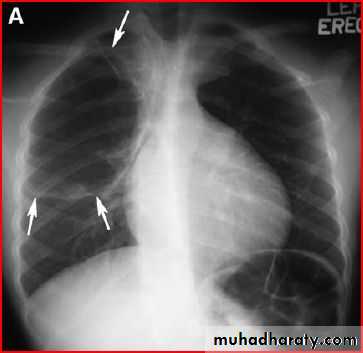

pneumothorax

Tention pneumothorax ( shifting mediastinum )

Endotracheal tubeSo, +ve pressure ventilation complicated to pneumothorax

Rt. Total lung collapse